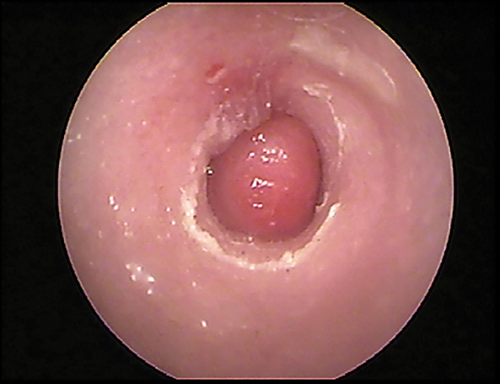

Globoid brown-to-black mass occluding internal ear canal.

FIGURE 14

Wax plug (ceruminolith) on the eardrum

Wax plug in an ear. Accumulations of wax (cerumenolith) commonly  show up at the eardrum when the eardrum epithelial surface has been previously compromised.  Dried oily medication and inspissated mucus from the bulla can look similar.

Cerumen accumulation against the eardrum, in addition to stenosis and hyperplasia, can impede conduction of sound waves and result in temporary hearing loss. Ceruminoliths require mechanic removal, preferably with endoscopic grasping forceps through a video otoscope with the patient anesthetized. If the eardrum is not intact, exudates such as mucus and pus can leak into the horizontal canal and inspissate at the eardrum. This condition can look like a ceruminolith. The mucoid secretions dissolve in water and can be removed with a water or saline flush of the horizontal canal.